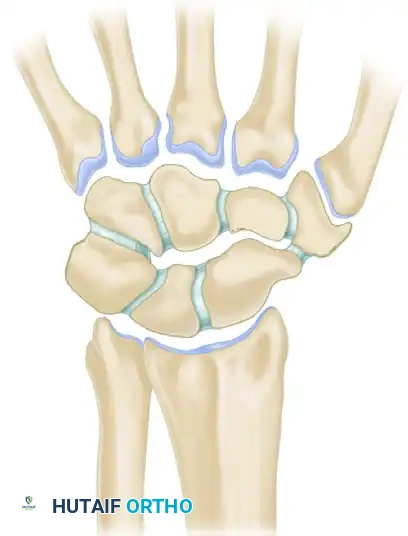

The human wrist is an intricate biomechanical marvel, comprising eight carpal bones, multiple articulating surfaces, and a complex network of intrinsic and extrinsic ligaments. The diagnosis of wrist conditions—whether acute traumatic injuries or chronic degenerative pathologies—demands a meticulous, systematic approach. For the orthopaedic surgeon, mastering the diagnostic algorithm is paramount to preventing long-term sequelae such as carpal collapse, chronic instability, and post-traumatic osteoarthritis (e.g., Scapholunate Advanced Collapse [SLAC] or Scaphoid Nonunion Advanced Collapse [SNAC]).

To accurately diagnose wrist instability, the surgeon must possess a profound understanding of carpal kinematics. Two primary biomechanical models dominate contemporary orthopaedic thought: Taleisnik’s Columnar Concept and Lichtman’s Ring Concept.

Taleisnik proposed that the wrist functions via three distinct longitudinal columns:

* The Central (Flexion-Extension) Column: Comprises the entire distal carpal row (trapezium, trapezoid, capitate, hamate) and the lunate. This column is primarily responsible for the transmission of flexion and extension forces.

* The Lateral (Mobile) Column: Consists solely of the scaphoid, which bridges the proximal and distal rows, providing critical stability and mobility.

* The Medial (Rotary) Column: Comprises the triquetrum, functioning as a pivot point for carpal rotation.

Lichtman’s Ring Concept

Lichtman expanded upon carpal kinematics by describing the carpus as an oval ring. In this model, the proximal and distal carpal rows act as semirigid posts stabilized by robust interosseous ligaments.

* Normal, controlled mobility occurs primarily at the scaphotrapezial and triquetrohamate joints.

* Pathomechanics: Any break in this ring—whether osseous (e.g., scaphoid fracture) or ligamentous (e.g., scapholunate dissociation)—destabilizes the kinematic chain.